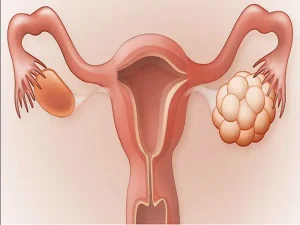

سندروم تخمدان پلیکیستیک یا PCOS، یکی از شایعترین اختلالات هورمونی در میان زنان در سنین باروری است که بر چرخه قاعدگی، تخمکگذاری و حتی باروری

تنبلی تخمدان یا سندرم تخمدان پلیکیستیک، یکی از شایعترین اختلالات هورمونی در میان زنان در سنین باروری است که بر عملکرد طبیعی تخمدانها تاثیر میگذارد.

فیبروم و کیست تخمدان دو مشکل شایع در ناحیه زنان هستند که اغلب با یکدیگر اشتباه گرفته میشوند، اما از نظر ساختار، منشا و تاثیرات